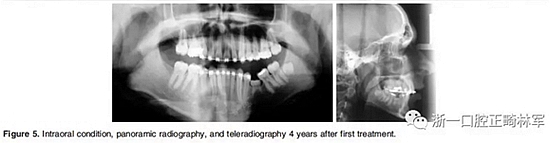

4.影像檢查:右上前磨牙和左下第二前磨牙缺失(Figure 4)。在另一名牙齒矯正醫(yī)師治療4年后,患者在19歲時被轉(zhuǎn)診給我們。他的咬合特征與他的初始狀態(tài)非常相似(Figure 5)